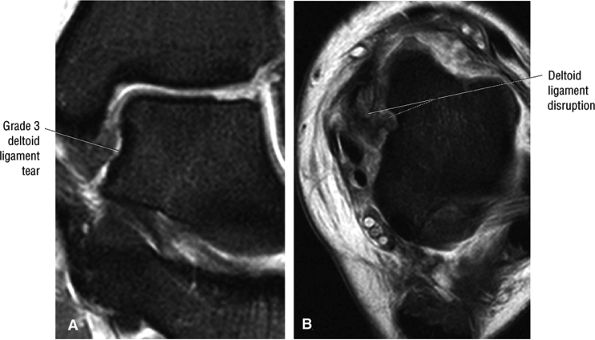

The deltoid ligament consists of superficial and deep layers.

fascicle inserts onto the superior border of the calcaneona vicular ligament. The deep part of the deltoid, which is rectangular, consists of a small anterior component (the anterior tibiotalar ligament) and a strong posterior component (the posterior tibiotalar ligament) (Fig. 5.64). The posterior tibiotalar ligament represents the strongest part of the entire medial ligament complex. The deep portion of the deltoid ligament, covered by synovium, is intra-articular.